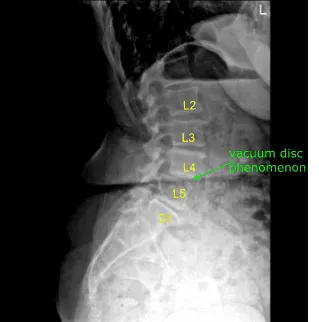

Un paciente acudió a una clínica de neurocirugía con signos y síntomas de estenosis lumbar con claudicación neurogénica y caída del pie derecho. Las imágenes mostraron estenosis severa en L4-5 central y L5-S1 en el izquierdo. Se recomendó cirugía para descomprimir la columna lumbar.

Estaban posicionados boca abajo sobre un chasis Wilson. Todos los puntos de presión estaban cuidadosamente acolchados. La zona lumbar se limpió con clorhexidina. Se utilizó una aguja espinal de calibre 22 y fluoroscopia para localizar el nivel L4-5.